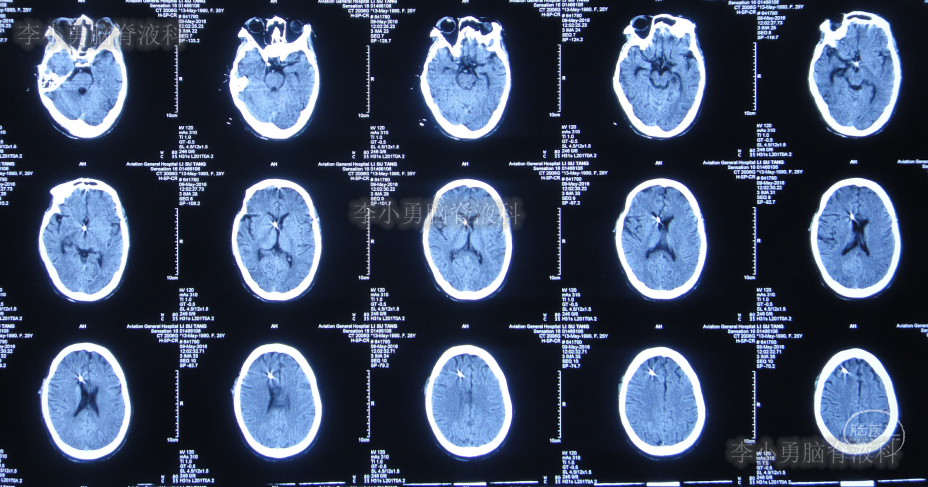

入院治疗18天即2016年5月23日,进行了脑室腹壁外引流术,术前与术后当天头颅CT(图-14)。

图-14:2016年5月23日术前术后头颅CT对比

入院治疗24天即2016年5月29日,头颅CT示脑室有变小(图-15)。

图-15:2016年5月29日头颅CT

入院治疗33天即2016年6月7日,头颅CT示脑室变大(图-17)。

图-17:2016年6月7日头颅CT

入院治疗40天即2016年6月14日,患者引流脑脊液量变少考虑再次出现堵管(图-18)。

图-18:2016年6月14日头颅CT

进行了脑室引流管调整术,术后当天查头颅CT示脑室引流术状态(图-19)。

图-19:2016年6月14日头颅CT